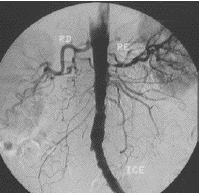

I started out as a fileroom clerk 15 years ago....I decided that I was working to hard, and not making enough money so I went back to school to become a Tech. I now work performing Interventional/Specials procedures, Mammography and basically anything else they schedule me to do! I love my job and the great people I meet. NEVER a dull moment. I recently switched places of employment after 15 years. Change is good! If you have any offers I can't refuse...check out my resume. RESUMEClick here

Being a Mammographer has really opened my eyes to the very real threat of Breast Cancer. I am told that the Bay Area has the highest rate of breast cancer. Believe it or not Ladies.....we really do compress because we care. Check out this link to find out how to get a FREE breast exam and/or Mammogram if you live in the Bay Area in California. BCEDP